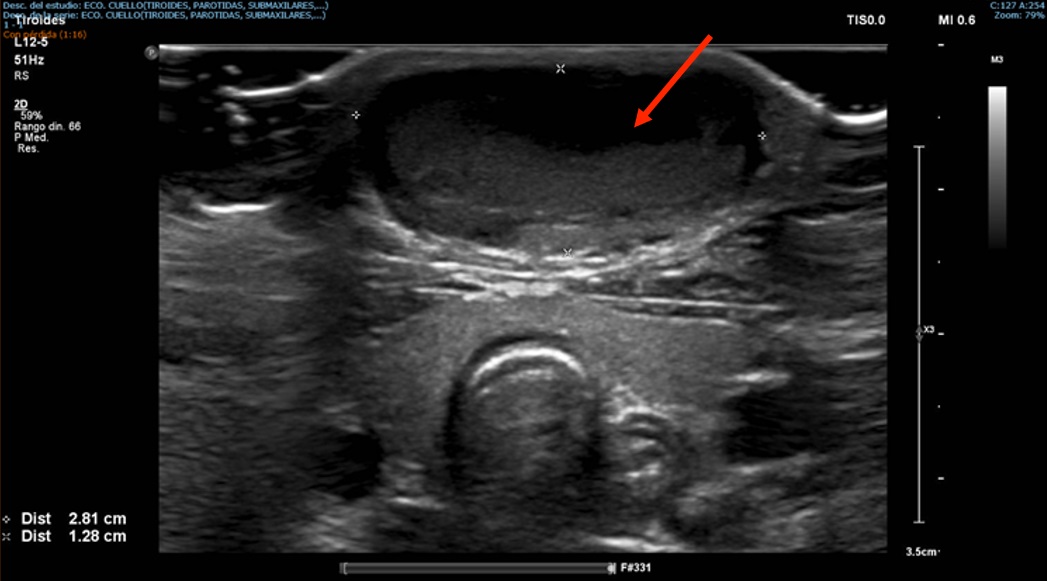

Niño de 4 años que consulta en Urgencias por tumoración cervical en línea media anterior del cuello de 3 meses de evolución que ha ido en aumento (Figura 1). Durante la última semana ha presentado dolor y enrojecimiento en la zona. No asocia distrés respiratorio, disfagia ni fiebre. No presenta antecedentes médicos relevantes.

A la exploración destaca una masa cervical anterior móvil, blanda, que aumenta de tamaño con la deglución.